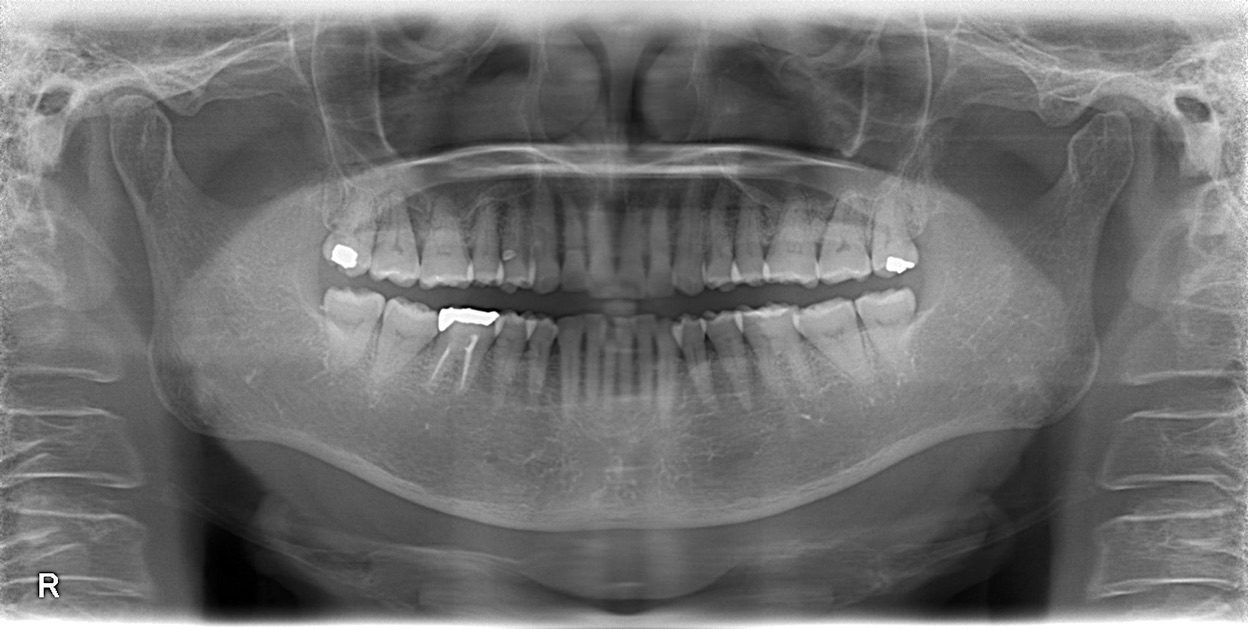

右上が痛い、ということで来院されました。

一見問題なさそうですが、歯周病の検査をすると右上の奥の歯に重度の歯周病が確認できました。

歯周病検査には専用の器具を使用すれば状態のほとんどを理解することは可能ですが、役立つのがCT検査です。

レントゲンではうまく描くことはできませんが、、、

CT撮影を行うと、歯、骨が立体で描かれます。

オレンジでマークしたところが黒く染まっているのがお分かりいただけるかと思います。

本来は白色〜鼠色で描かれ、骨があるべき部位です。